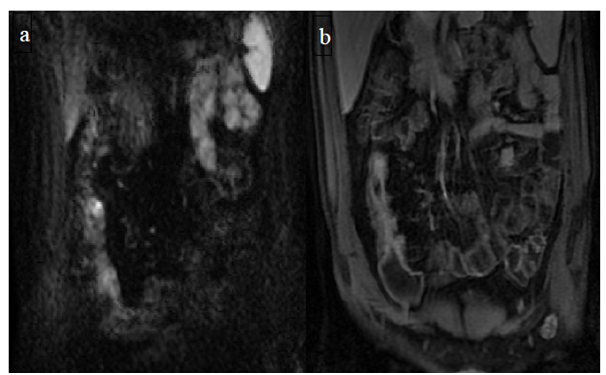

Figure 4 (a) Coronal SSFSE (singleshot fast spin echo) T2-weighted image with fat suppression (b) axial FIESTA (fast imaging employing steady-state acquisition) image show wall thickening (white arrow) and stenosis of the lumen in the terminal ileum. Note the prestenotic dilatation in b (white arrowhead). (c) Neoterminal ileum wall is thickened and has high signal on diffusion-weighted (DW) image (b= 800 s/mm2) (white arrow) and dark signal (black arrow) on the apparent diffusion coefficient (ADC) map in (d) indicating restricted diffusion. (e,f) ADC value measurement from the wall of the terminal ileum on magnified DW image. (e) and corresponding ADC map (f): ADC value = 1.20 × 10-3 mm2/s

Figure 5 Comparison of coronal (a) and axial (c) DWI sequences with the respective

after contrast medium injection (b, d).